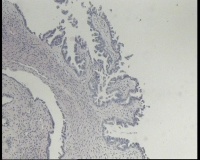

求会诊!左侧卵巢囊肿,够交界性浆液性囊腺瘤吗?

左侧卵巢囊肿大小约6.5x6.0厘米

碎囊壁组织5.0厘米一堆,壁厚0.1—0.4厘米,局灶囊壁见散在赘生物0.3,0.5厘米。另见完整小囊肿1.5x1.0厘米,无内容物,壁厚0.1厘米,内壁附0.8x0.7x0.4厘米赘生物,颗粒状

交界性浆液性乳头状囊腺瘤